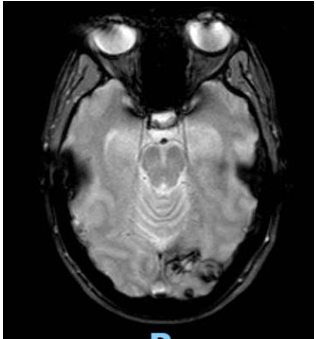

Posteriormente se solicita interconsulta al Servicio de Oncología y se realiza RMN de cerebro (Imagen 3) descartándose secundarismo en este órgano (se informó área de aspecto secuelar con depósitos de hemosiderina en secuencia de gradiente a nivel de la corteza occipital izquierda. La misma no presenta áreas de restricción o realces tras la administración de contraste ev.)

Imagen 3. RMN de cerebro al diagnóstico